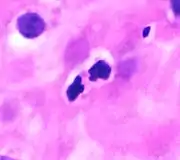

These cells are eosinophilic or "acid-loving" due to their large acidophilic cytoplasmic granules, which show their affinity for acids by their affinity to coal tar dyes: Normally transparent, it is this affinity that causes them to appear brick-red after staining with eosin, a red dye, using the Romanowsky method.[4] The staining is concentrated in small granules within the cellular cytoplasm, which contain many chemical mediators, such as eosinophil peroxidase, ribonuclease (RNase), deoxyribonucleases (DNase), lipase, plasminogen, and major basic protein. These mediators are released by a process called degranulation following activation of the eosinophil, and are toxic to both parasite and host tissues.

In normal individuals, eosinophils make up about 1–3% of white blood cells, and are about 12–17 micrometres in size with bilobed nuclei.[3][5] While they are released into the bloodstream as neutrophils, eosinophils reside in tissue.[4] They are found in the medulla and the junction between the cortex and medulla of the thymus, and, in the lower gastrointestinal tract, ovaries, uterus, spleen, and lymph nodes, but not in the lungs, skin, esophagus, or some other internal organs under normal conditions. The presence of eosinophils in these latter organs is associated with disease. For instance, patients with eosinophilic asthma have high levels of eosinophils that lead to inflammation and tissue damage, making it more difficult for patients to breathe.[6][7] Eosinophils persist in the circulation for 8–12 hours, and can survive in tissue for an additional 8–12 days in the absence of stimulation.[8] Pioneering work in the 1980s elucidated that eosinophils were unique granulocytes, having the capacity to survive for extended periods of time after their maturation as demonstrated by ex-vivo culture experiments.[9]